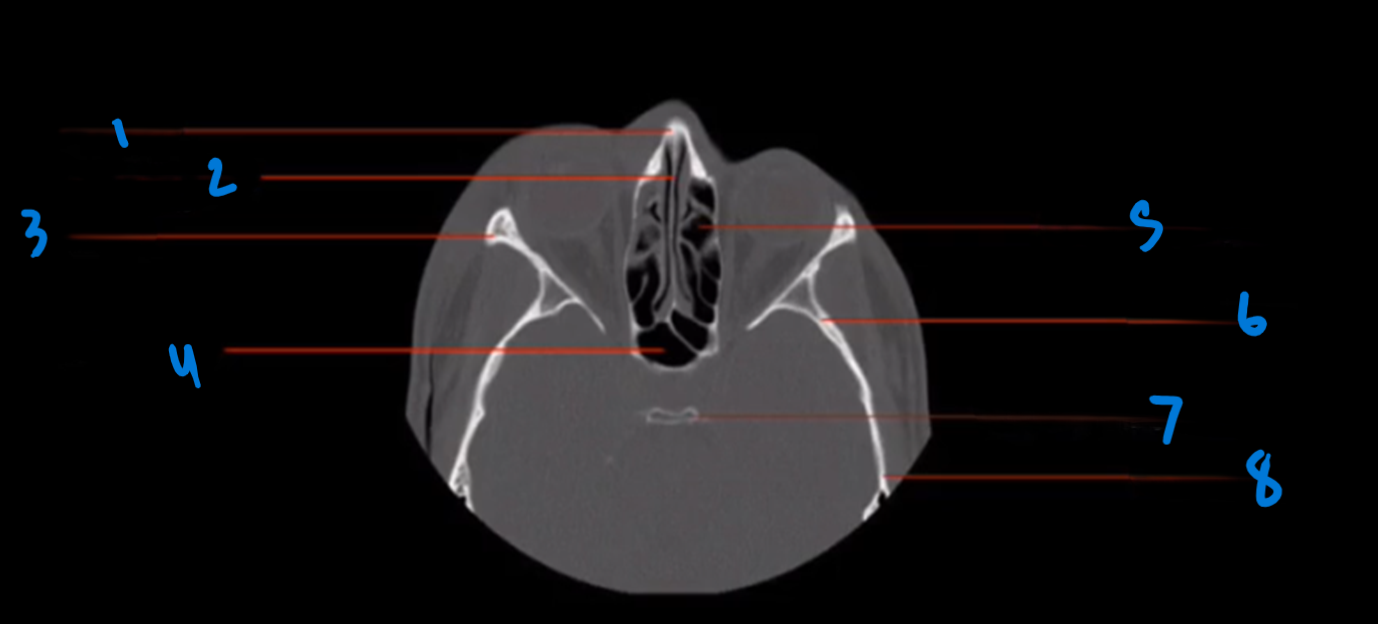

Landmark 1

Lacrimal Duct

Landmark 2

Maxillary Sinus

Landmark 3

Lateral Pterygoid Process

Landmark 4

Mandible

Landmark 5

Mastoid Air Cells

Landmark 6

Pony tail

Landmark 7

Maxilla

Landmark 8

Deviated Nasal Septum

Landmark 9

Medial pterygoid Process

Landmark 10

Landmark 11

Occipital Condyle

12

Foramen Magnum